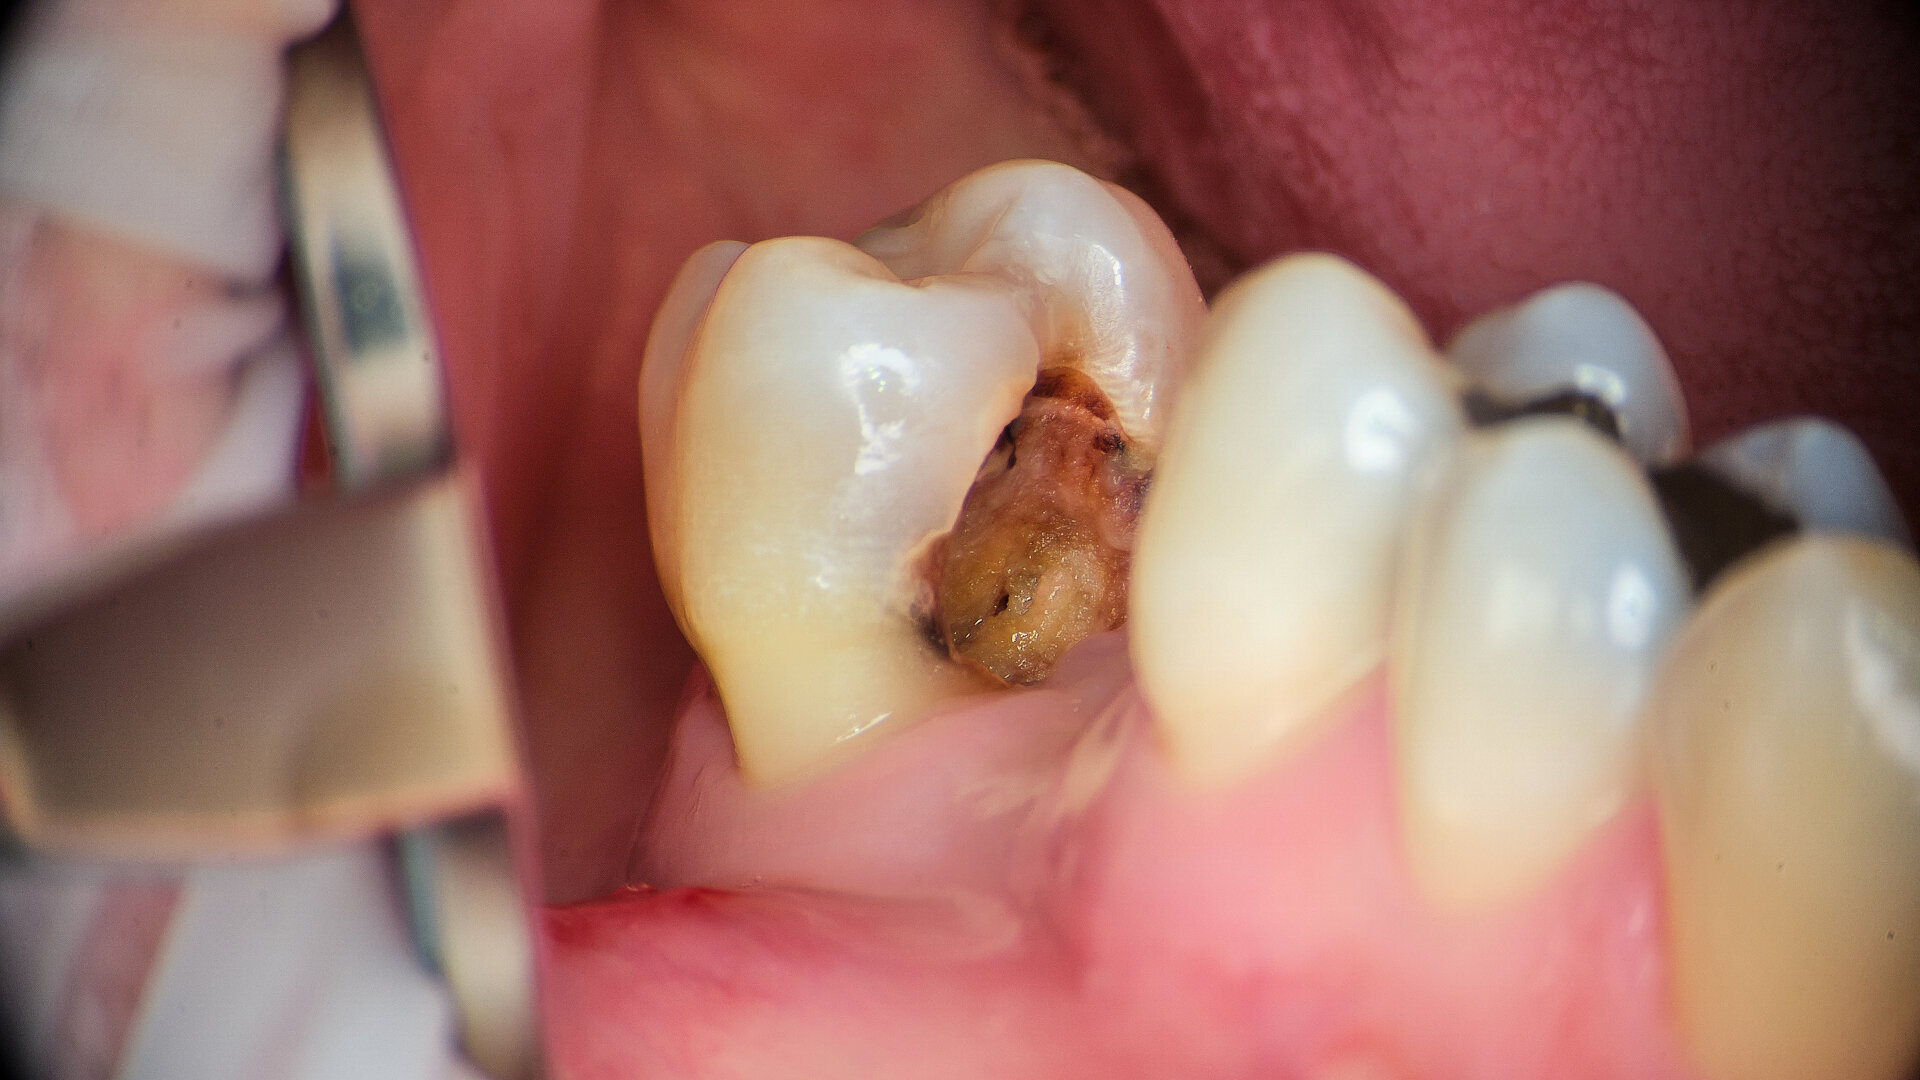

Case 1

A 43-year-old patient came to our office having been referred for endodontic treatment. During oral examination, a deep carious lesion in tooth #27 was visible. Radiographic examination confirmed the diagnosis (Fig. 6). After gingivectomy with a gingiva trimmer bur (JOTA), which was necessary in order to create space for proper isolation (Figs. 7–9), the cavity was cleaned and prepared for build-up.